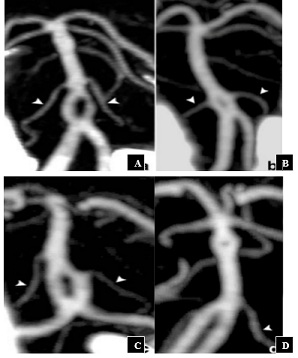

This can occur over the entire height of the artery but predominates in the proximal segment [5]. A classification based on the relationship between the fenestration and the origin of the Anterior Inferior Cerebell Ararteries (AICA) distinguishes 04 types (Figure 4) [6,7]

• Type I: the fenestration is located up stream of the origin of the AICA (this is the case of our patient);

• Type II: the two AICA s are born symmetrically on the fenestration;

• Type III: emergence of a single AICA on the fenestration;

• Type IV: the fenestration is located down stream from the origin of the AICA.

Figure 4 : Classification of basilarartery fenestrations. According to Gao, et al. [7] ; Type I (A): Fenestration before the emergence of the AICAs, Type II (B): Emergence of the two AICAs on fenestration, Type III (C): Emergence of a single AICA on fenestration, Type IV (D): Fenestration down stream from the origin of the AICAs.